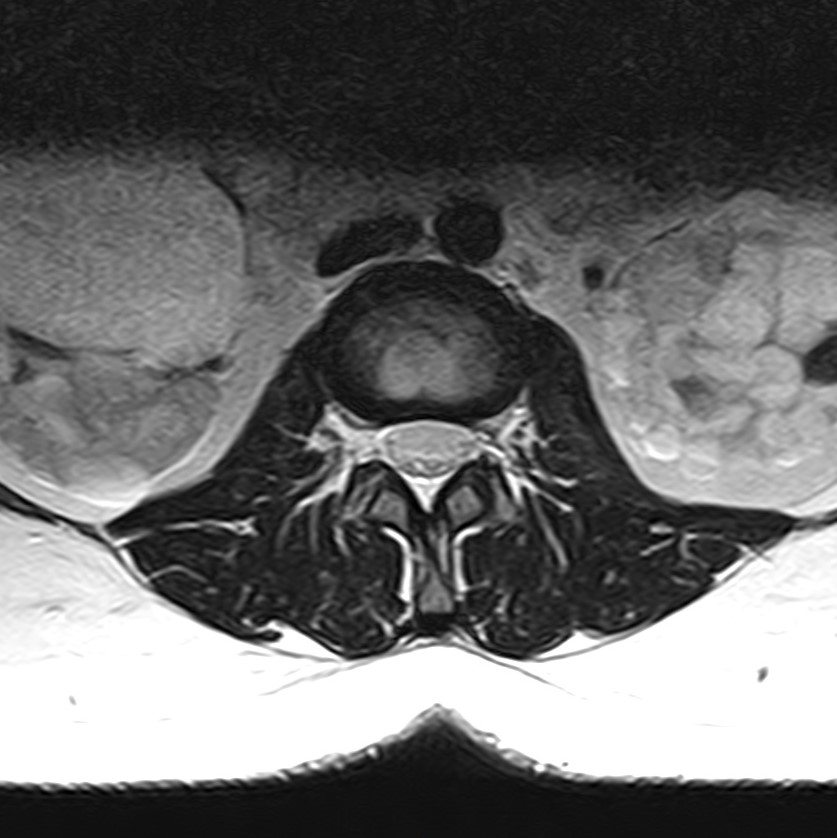

Наиболее точным и эффективным способом диагностики причин появления болей в нижней части спины является МРТ пояснично-крестцового отдела позвоночника. С помощью данного метода можно оценить состояние всех анатомических структур позвоночного столба на исследуемом уровне, безошибочно выявить происхождение болевого синдрома и назначить своевременное лечение.

Многим пациентам интересно, что показывает МРТ пояснично-крестцового отдела. Высокая детальность получаемых с помощью МР-диагностики изображений позволяет с точностью выявить следующие заболевания, локализующиеся в области поясничного отдела позвоночника:

• протрузии и грыжи межпозвонковых дисков;

• дегенеративные заболевания: остеохондроз, спондилез, спондилоартроз;

• последствия перенесенных травм, такие как компрессионные переломы, подвывихи и смещения позвонков;

• новообразования первичного и вторичного генеза;

воспалительные и деструктивные изменения позвонков и окружающих мягких тканей.